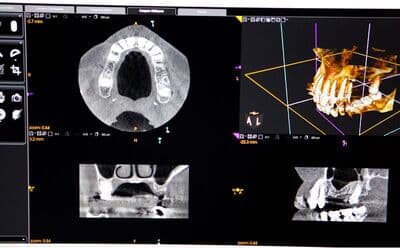

サイナスリフトの症例

【症例】サイナスリフトで骨を増やし、奥歯の支えを回復したインプラント治療

本症例の患者様は、右側の歯を抜歯した後そのまま放置していたことで噛み合わせが大きく乱れ、右上の歯周病が進行して抜歯に至りました。抜歯後は上顎洞に近接して骨量が著しく不足していたため、サイナスリフトによって新たな骨を増やし、インプラントを支える土台を再建しました。十分な骨量を確保することで、奥歯の咬合支持を回復した症例です。

before

after

治療内容 サイナスリフト、インプラント、矯正治療

治療期間 10ヶ月

治療回数 4回(他、抜糸、術後3ヶ月後、1年後の経過観察等を除く)

治療費用 3,300,000円(税込、サイナスリフト他、矯正治療を含む)

症例から言えること

本症例は、抜歯後の欠損部を放置すると歯が傾斜し、咬合支持が失われることで噛み合わせ全体が乱れ、別の部位の歯周病が急速に悪化することを示しています。さらに、こうした連鎖は将来的な大きな咬合崩壊につながる可能性があります。一方、骨量不足があってもサイナスリフトによりインプラントを支える骨を再建することで、機能を回復し、咬合の安定を取り戻すことが可能です。複雑な症例ほど、早期の診査・診断と適切な処置が咬合崩壊を防ぐ鍵となります。